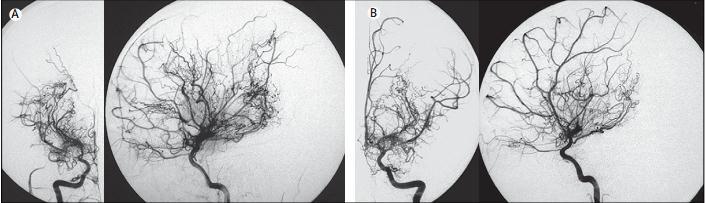

烟雾病是一种原因不明、慢性进行性的脑血管闭塞性疾病。主要表现为单侧或双侧颈内动脉远端、大脑中动脉和大脑前动脉近端狭窄或闭塞,伴脑底部和软脑膜烟雾状细小血管形成。本病于1961年发现于日本。因脑血管造影显示的异常细小血管形似烟雾,在日语中“漂浮的烟雾”发音为moyamoya,因此又称为“moyamoya disease”病。

烟雾病这一诊断仅是神经放射学诊断,不是病因诊断。凡无明确病因出现反复发作性肢体瘫痪或交替性双侧偏瘫的患儿,以及自发性脑出血或脑梗死的青壮年,不论其病变部位位于幕上还是幕下,均应首先考虑到此病的可能。除详细询问病史外,尚需要其他辅助检查如血常规、脑脊液血清钩端螺旋体凝溶试验、结核菌素皮试等。由于脑电图及CT 检查均没有特异性,故早期诊断比较困难。最终确诊此病,有赖于脑血管造影,有些患者就是在脑血管造影中无意发现而确诊的。